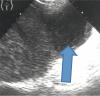

Subcapsular hematoma of the spleen (arrow)

Fig. 15